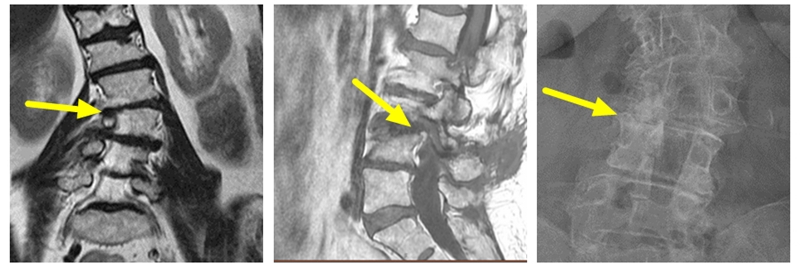

MRI可见局部弯曲凹侧神经根明显受压,腰椎X线可见椎体存在侧方滑移伴凹侧骨质增生硬化。

予患者行L3/4节段椎间孔减压,后路MIS固定。术后患者下肢疼痛症状完全消失。

术前MRI示L4/5左侧神经根管狭窄

行L4/5,L5/S1两个节段减压融合内固定术,术后患者下肢症状完全消失。